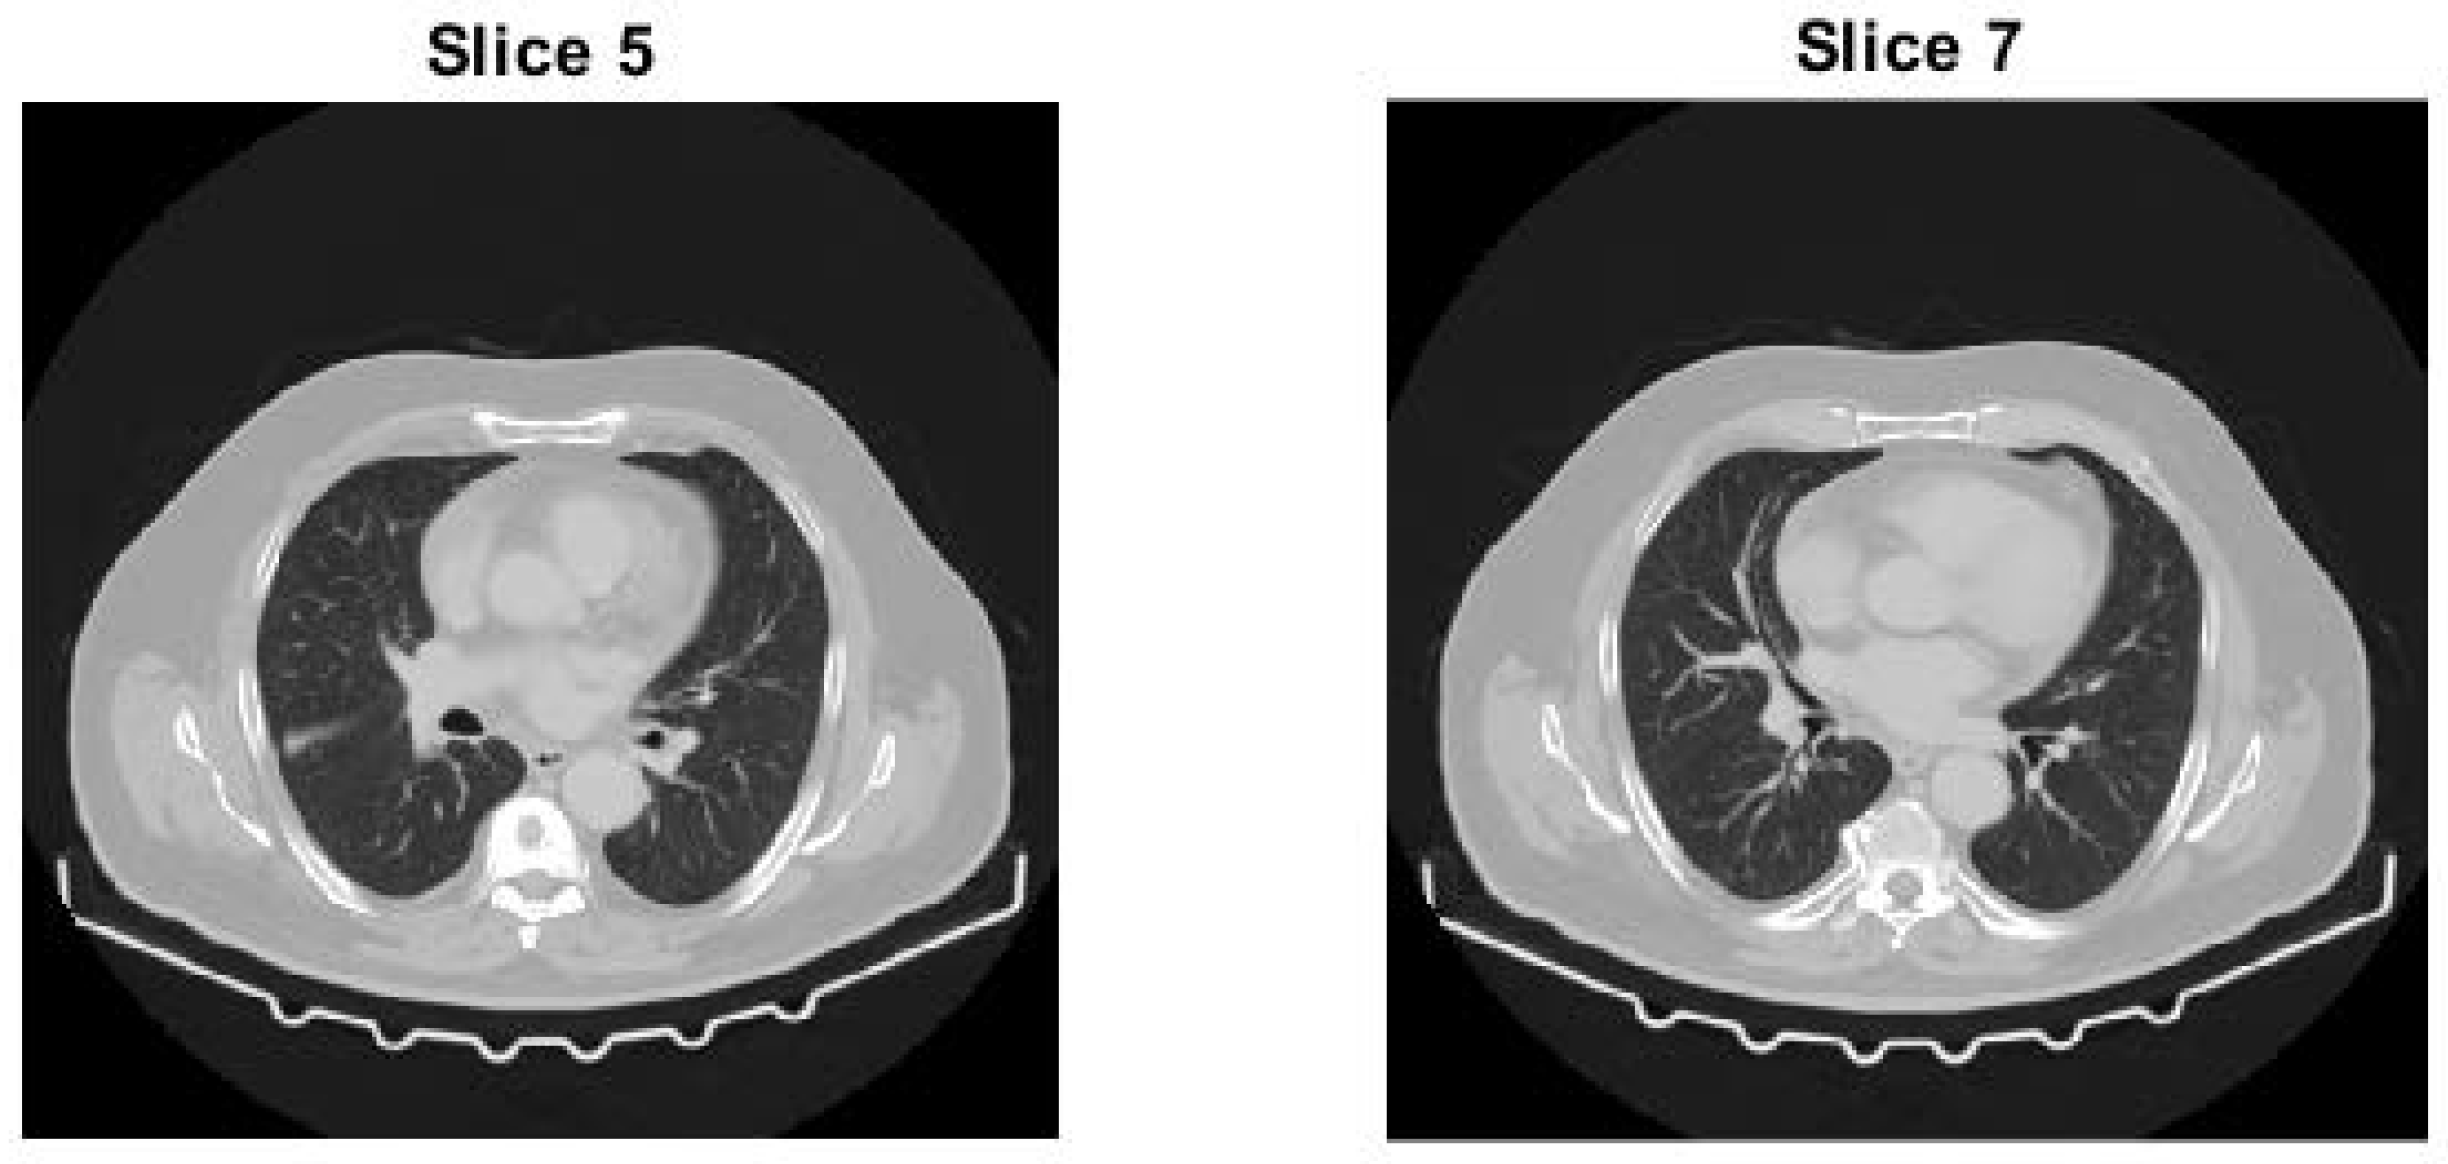

- Test image 3 is a 3D sub-volume extracted from a high-resolution CT scan of a human body, stored in DICOM format as a 16-bit unsigned integer (uint16) volumetric dataset.

4.3. Test Image 3

4.3.1. Preprocessing of Test Image 3

4.3.2. Whole Test Image 3

4.3.3. Test Slice of Test Image 3